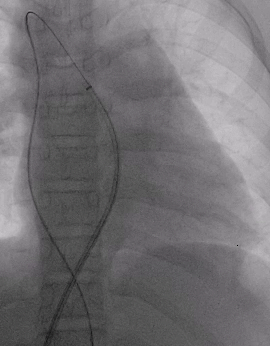

建立输送轨道

导管导丝送入左上肺静脉

加硬导丝送入左上肺静脉,送入14F输送鞘

送入BDASD-I 14可降解ASD封堵器

展开左右盘面

左盘展开

右盘展开